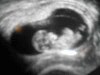

Bild zu Frauenarzttermin - Forum für Juli - Mamis

das ist soooo schön! Freu mich für dich das alles supi ist!!!!